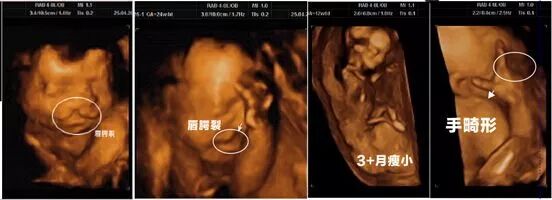

叶酸缺乏可增加母体发生胎盘早剥,贫血以及妊娠高血压等疾病的风险,可表现为头晕、乏力、精神萎靡以及食欲下降、腹泻等消化系统症状;对胎儿的危害可引起低体重、唇腭裂、心脏缺陷,流产、早产、神经管畸形等。

孕前补充叶酸有很多的好处,如:叶酸有助于预防神经管畸形,包括脊柱裂和无脑儿等非常严重的出生缺陷。中国北京大学生育健康研究所的一项研究显示,服用叶酸不仅可以有效预防神经管畸形,还可以减少新生儿15%的重大体表畸形、30%唇腭裂和35%先天性心脏病的发生。